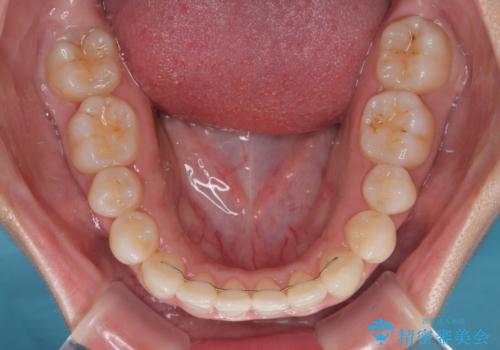

- 上下前歯のデコボコを気にして来院された患者様です。

上顎歯列が下顎の歯列に対して狭小であり、一部下顎の奥歯が上顎よりも外側に位置している状態でした。

上顎の急速拡大装置を使用して上顎骨を側方に拡大することで上顎歯列を拡大し、下顎歯列も拡大できるようにすることで、歯列を整えることとしました。